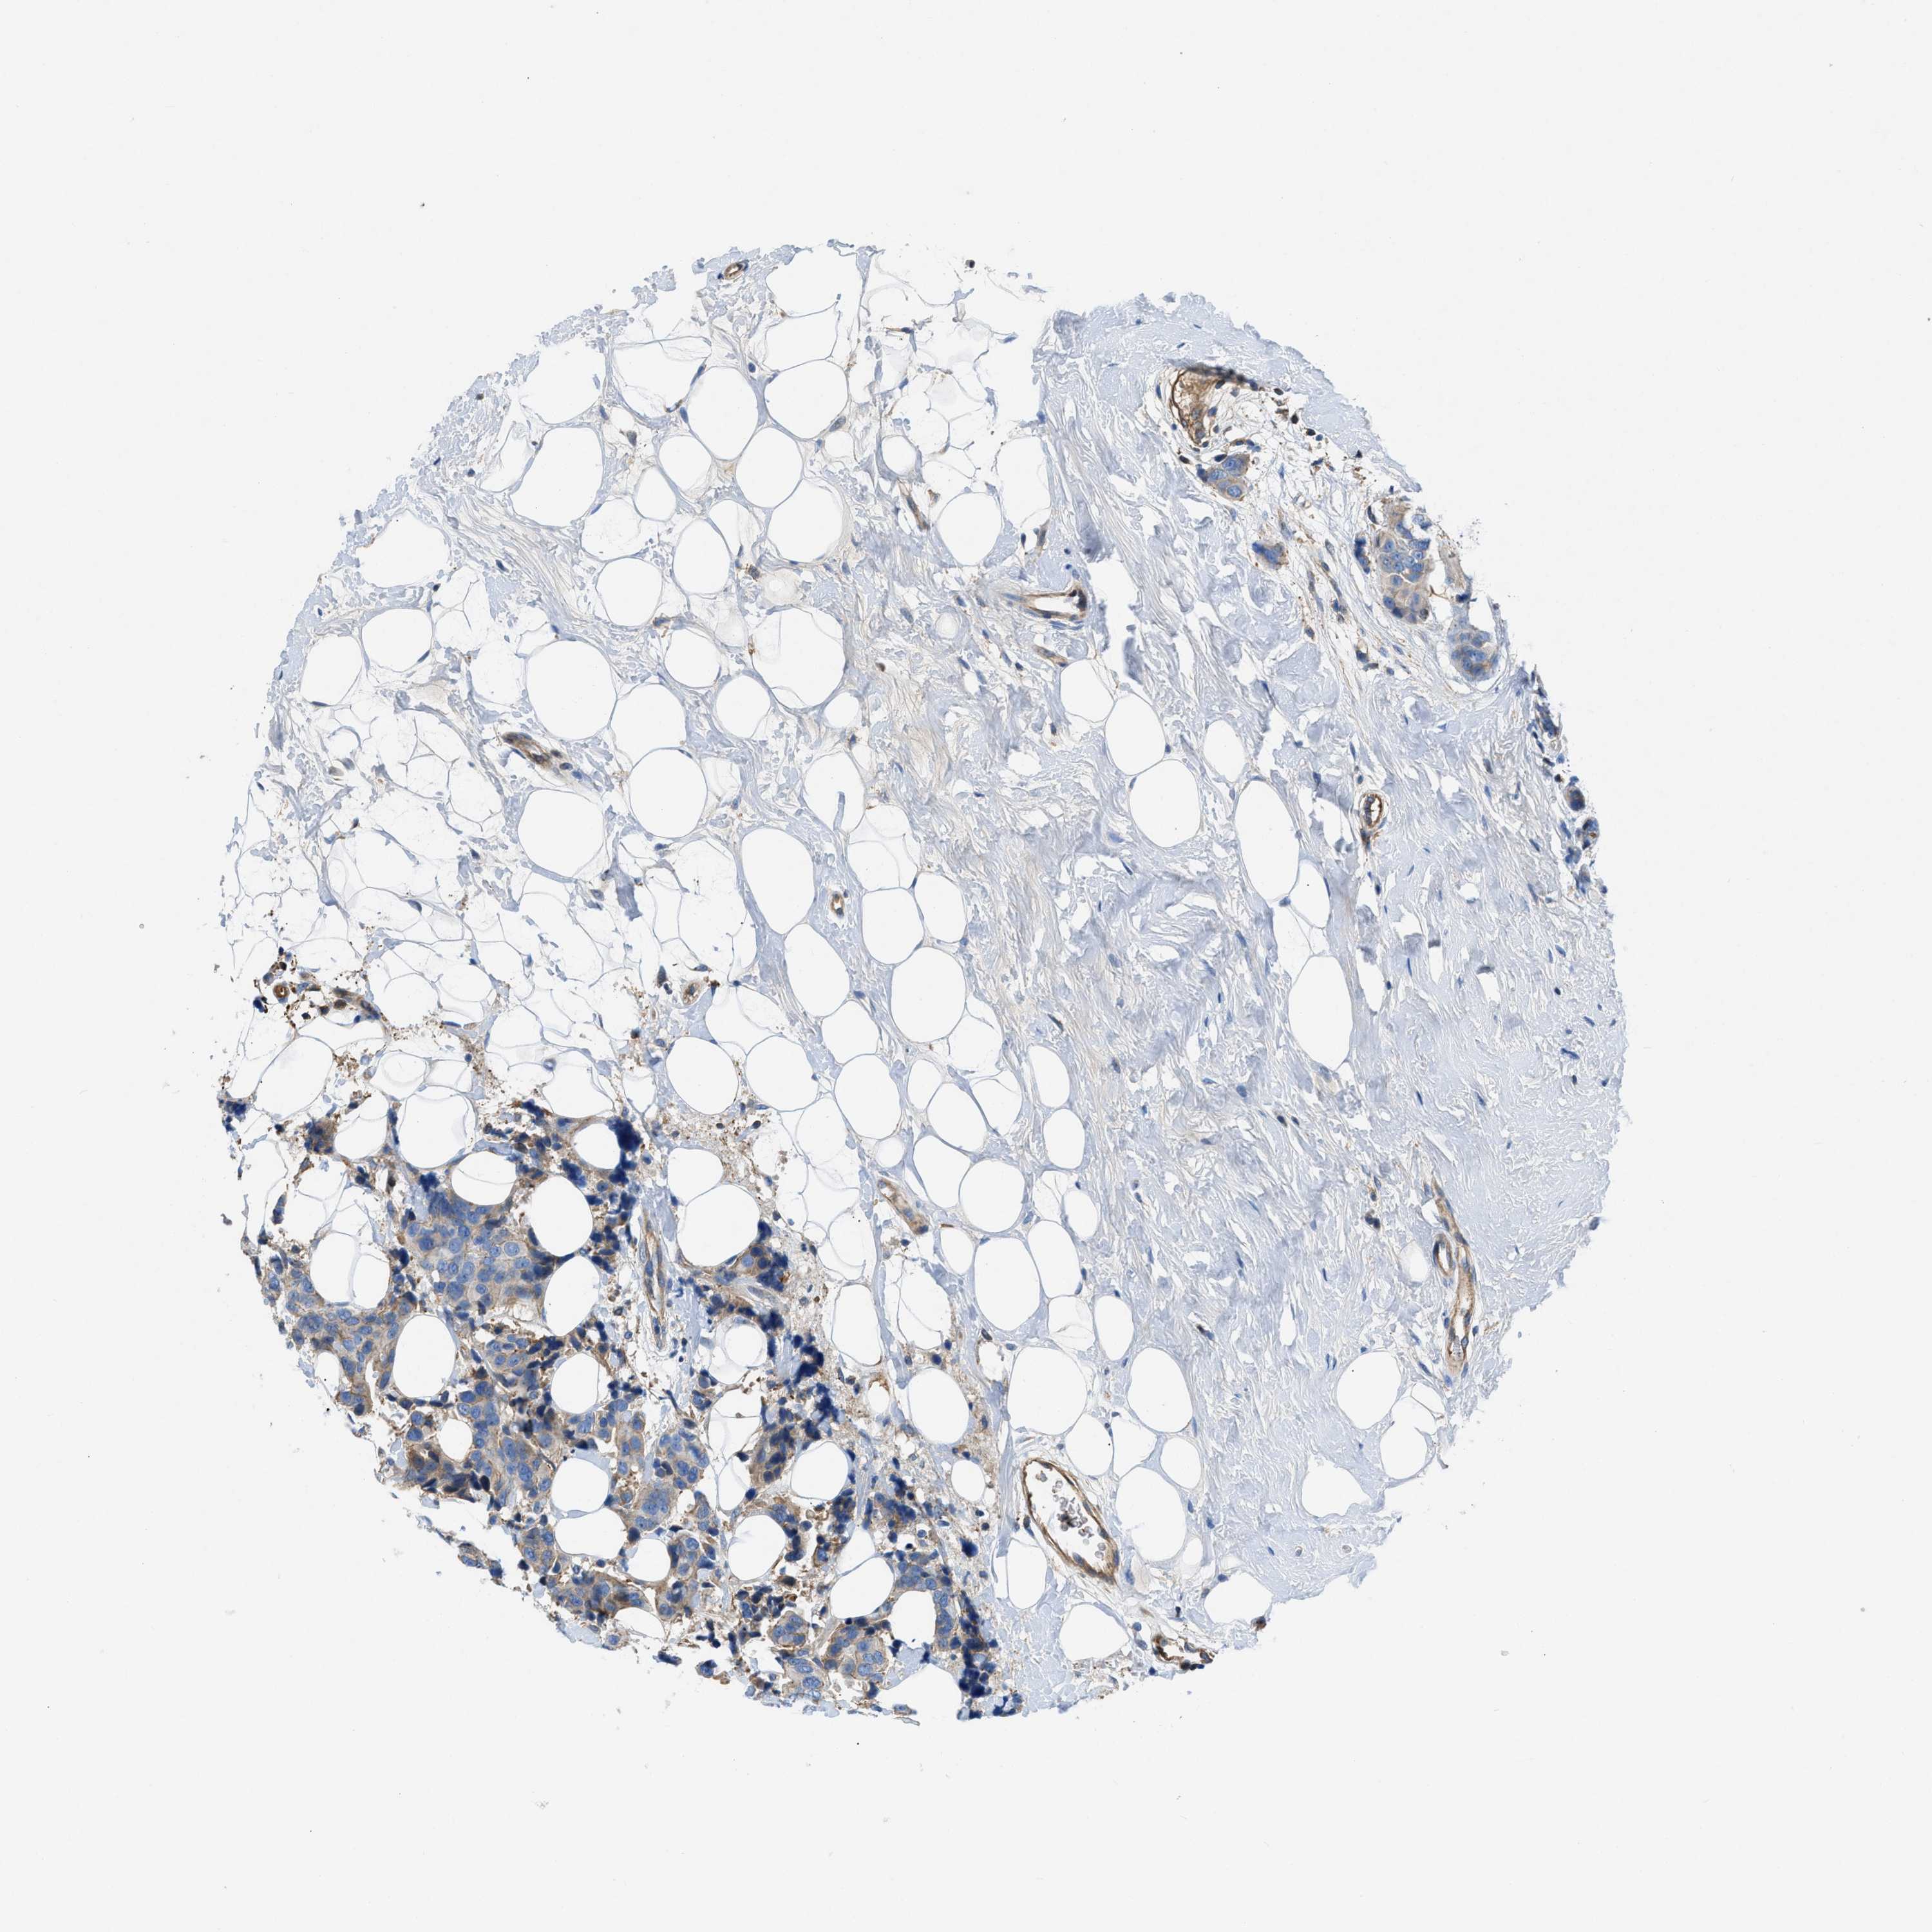

BRCA TCGA BRCA VALIDATION PROTEIN EXPRESSION